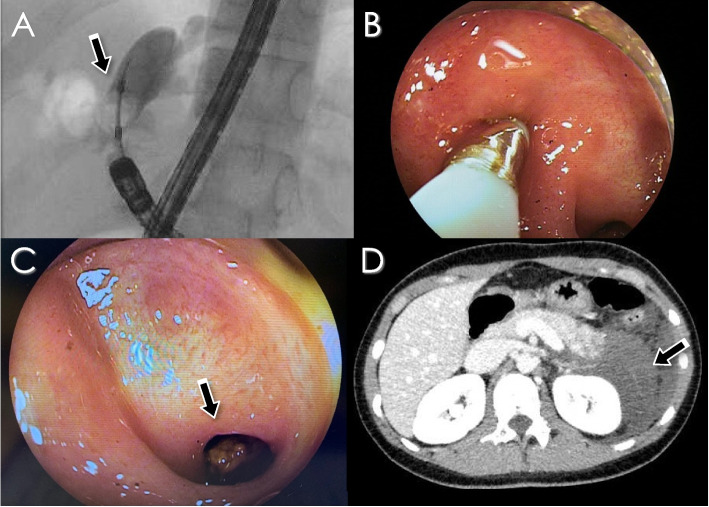

DB-ERC was attempted 8 times in 5 patients with hepatolithiasis. The median age of these patients at the time of primary surgery for CBD was 2 (0–3) years, and the average age at the first time of DB-ERC was 20 (9–36) years. The median duration from primary surgery to DB-ERC was 18 (8–36) years. There were no cases of bile duct plasty at primary surgery for CBD. In 2 of the 5 patients, the endoscope could not reach the porta hepatis due to a long jejunal loop and intestinal adhesion. One patient (Case 3) presented with severe acute pancreatitis induced by prolonged DB-ERC over 3 hours (Fig. 3). Although she fully recovered from pancreatitis 2 months after DB-ERC, asymptomatic IHBD stone recurrence was noted after 2 years, and the administration of UDCA was continued. The remaining two patients successfully improved.